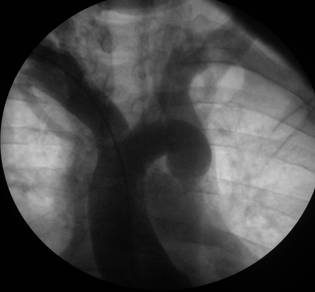

A 52-year-old obese white man was referred to our hospital because of increasing fatigue and exertional dyspnea. He had been well until 5 months previously. The patient had a medical history of dyslipidemia and hypertension. His hypertension was poorly controlled despite a combination of antihypertensive agents (beta-blocker and angiotensin receptor blocker). Physical examination showed blood pressure 140/90 in both arms, a heart rate of 74 beats/minute and an apical gallop sound (S4). Femoral pulses were palpable bilaterally but weak and delayed compared to the brachial pulses. His echocardiogram showed bicuspid aortic valve with minimal regurgitation, segmental wall motion abnormalities and mild mitral insufficiency. A cardiac silhouette at the upper limits of normal and notching of the ribs were observed on the chest radiography. Due to the significance of the cardiac dysfunction and his clinical presentation, the patient underwent a cardiac catheterization to evaluate his coronary artery disease. The left ventricular ejection fraction was significantly reduced (Ejection fraction: 30-35%). There was no evidence of mitral valve prolapse. Aortography showed a mildly dilated aortic root, minimal aortic valve insufficiency and a significant ring-like stenosis in the thoracic descending aorta (Figures 1 and 2). The gradient through this stenosis measured 80 mmHg. The coronary angiography was negative for significant focal coronary artery obstruction. The patient was then referred to cardiothoracic surgery. The procedure was done via left posterolateral thoracotomy from the fifth intercostal space. Since, the collaterals were well recognized before surgery, the procedure was achieved without major bleeding and any adverse event. Furthermore, the patient was adult and any minor bleeding has not resulted in requirement of blood transfusion. The coarctated segment was resected totally and end to end anastomosis of thoracic aorta was performed in a standart fashion. The coarctated segment was short in our patient and it was not difficult to get the two ends together without tension on the anastomosis so that we do not considered an interposition graft. The cross clamp time was 23 minutes and because the collaterals were left intact, any malperfusion syndrome has not occurred. Total hospital stay after procedure was only four days. After the 1-year follow-up visit, the patient was in good clinical condition.

Figure 1

Ascending aortography